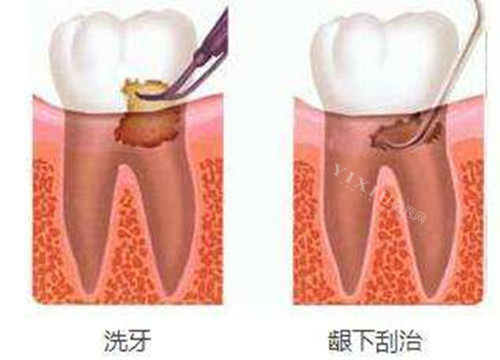

洗牙:

超声波洁牙:180元起/次

喷砂洁牙:260元起/次